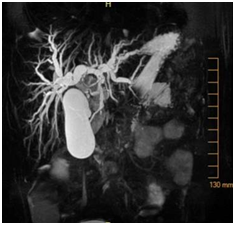

An 11-year-old girl with history of sickle cell trait and allergic rhinitis presented to the emergency department for pruritus. She had been evaluated at an urgent care clinic three weeks prior for generalized rash and pruritus, and was diagnosed with contact dermatitis. At current presentation, rash had resolved but she had persistent pruritus. No abdominal pain. She had scleral icterus, but family reported this was not uncommon as it occurred for over a year and seemed to get worse with her “seasonal allergies”. Initial assessment showed a thin nontoxic appearing girl with normal vital signs and an exam significant for icteric sclerae, excoriations but no rash, and a nontender abdomen with liver palpable 2cm below the right costal margin. Laboratory results showed elevations in direct bilirubin, alkaline phosphatase, and GGT. Ultrasound showed intrahepatic biliary dilation with an echogenic area in the common hepatic duct suggestive of sludge. She had a magnetic resonance cholangiopancreatography (MRCP) that showed diffuse dilation of the intrahepatic, common hepatic, and common bile ducts; a distended gallbladder; and a T2 hypodense lesion in common bile duct extending into common hepatic duct that was consistent with biliary sludge (Figure 1), with suspicion for choledochal cyst. She then had an upper endoscopy, which was significant for a lesion protruding from the ampulla that had the appearance of a blood clot. It was extracted after sphincterotomy, and noted to have a thin stalk-like attachment, measuring 1.3cm in length, which was partially resected and sent to pathology (Figure 2&3). Pathology was significant for a polypoid tumor with variable cellularity, and “tadpole” shaped cells having cytoplasmic cross striations, and a high proliferative index by Ki67 stain. These findings were diagnostic of a botryoid variant of embryonal rhabdomyosarcoma. She was started on chemotherapy with vincristine, adriamycin, and cyclophosphamide (VAC), and improved with this regimen. She has not required surgery or radiation (Figure 4A-4C).

Figure 2 Endoscopy showing lesion protruding from the ampulla that had the appearance of a clot versus mass.